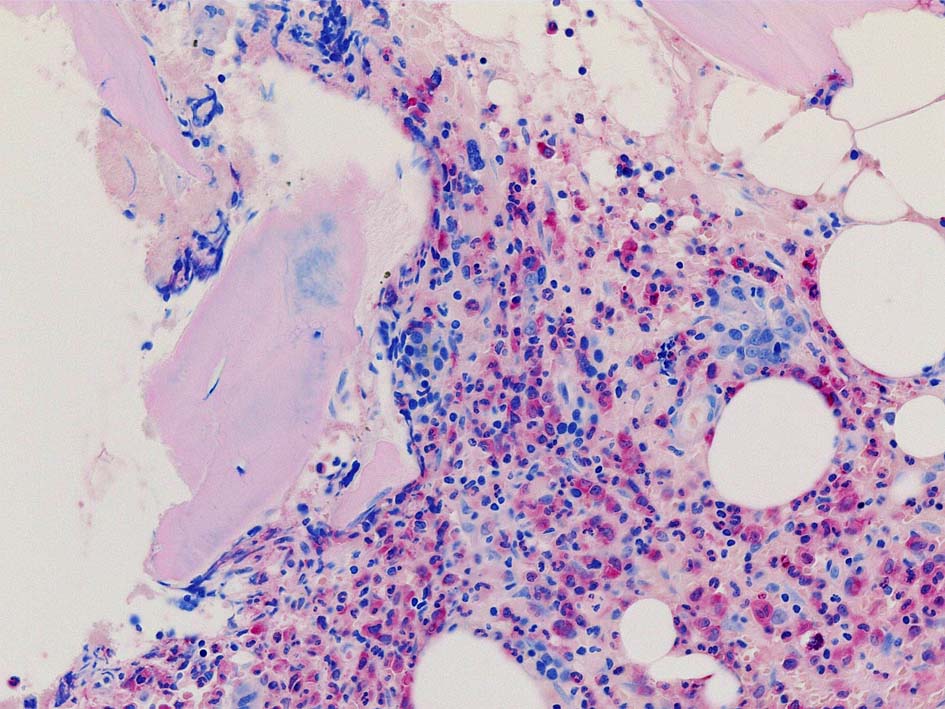

Case02; Meylofibrosis, overt fibrosis

77year-old female. 40歳時polycythemia veraと診断されていた.

[注] この症例は詳細は不明であるが, 過去にPVと診断されているため, PVに伴う二次性のmyelofibrosisの診断になる.

黒染する弾性線維の増生のほか, 赤く染まる膠原線維の増生が確認される. MF-2 fibrosis. 鍍銀染色の核染色をすると膠原線維の赤染がわからなくなるので行わない.